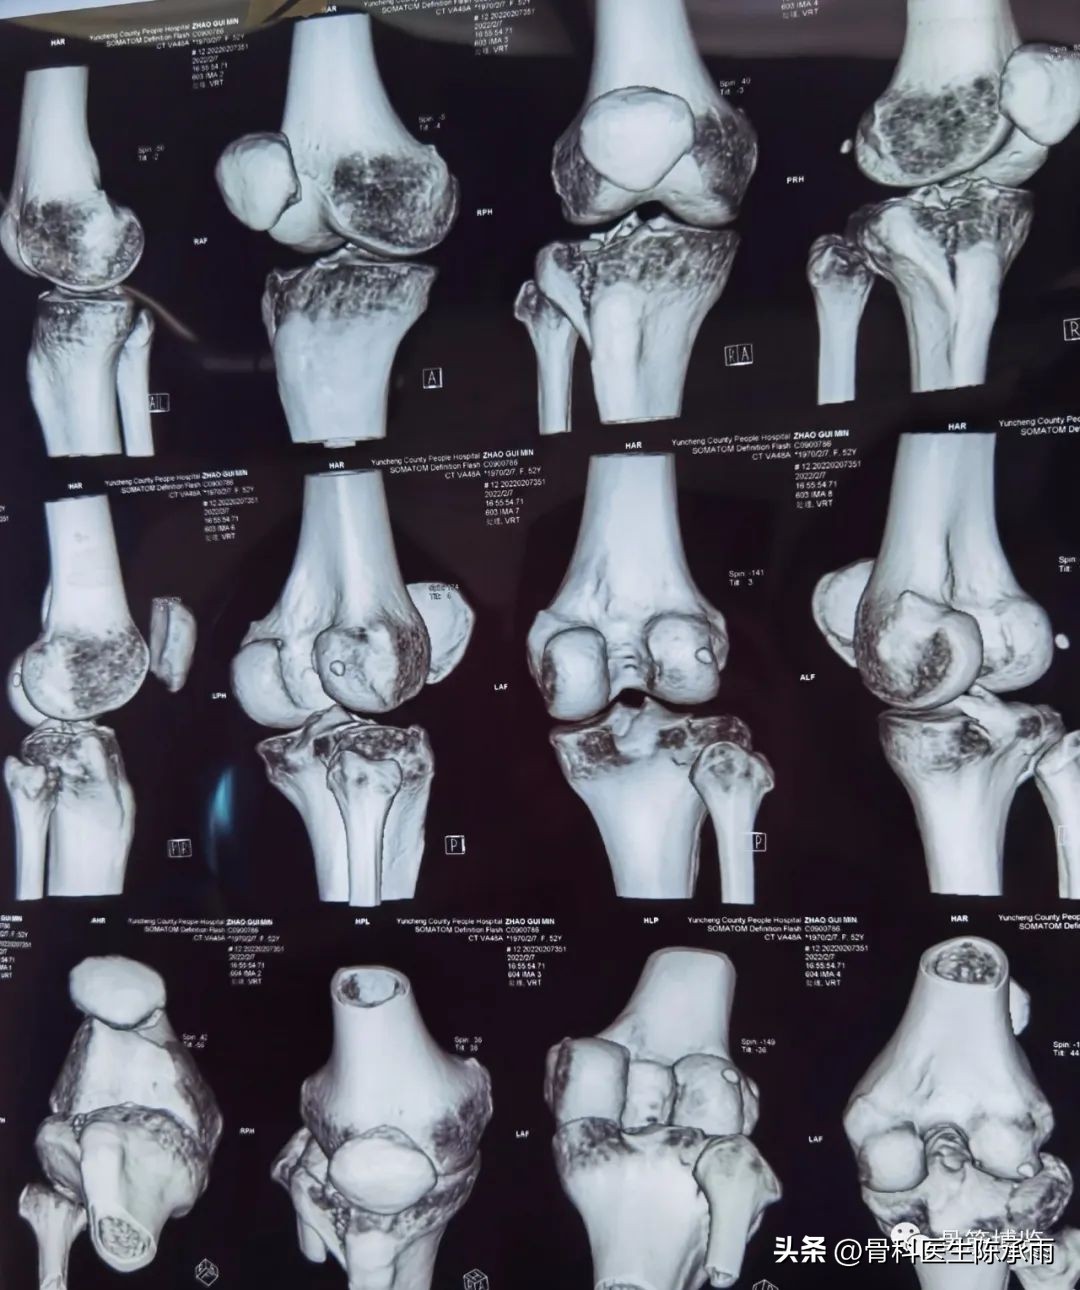

胫骨平台骨折的分型比较多,我们临床上常用的就是Schatzker分型和AO骨折的分型,还有骨折脱位的Hohi-Moore分型,这是我们常用的三个分型。

Schatzker分型来讲它一共分为六型:

一型 劈裂,

二型 劈裂塌陷,

三型 外髁的一个单纯塌陷,

四型 内髁的骨折,

五型 双髁的骨折,

六型 双髁伴干骺端的骨折,

对AO 分型来讲,现在这是AO推出来更详细的,再分为ABC。随着分型的增加,从A到C骨折的损伤程度是越来越重,治疗也越来越困难,从1到2 ,123也是这个规律,骨折的分型就是给我们表明了骨折的一个损伤的程度,治疗办法和损伤的特点。我们对于骨折脱位的分型,常用Hohi-Moore分型,这个是弥补了,Schatzker和AO分型的一些缺陷。